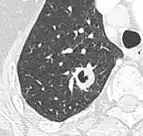

- Bubble-like lucencies in the nodule indicate cancer:[9]

.png)

- Vascular convergence is where vessels converge to a nodule without adjoining or contacting the edge of the nodule, and is mainly seen in peripheral subsolid lung cancers.[9] It reflects angiogenesis.[9]

Air bronchograms is defined as a pattern of air-filled bronchi on a background of airless lung, and may be seen in both benign and malignant nodules, but certain patterns thereof may help in risk stratification.[9]